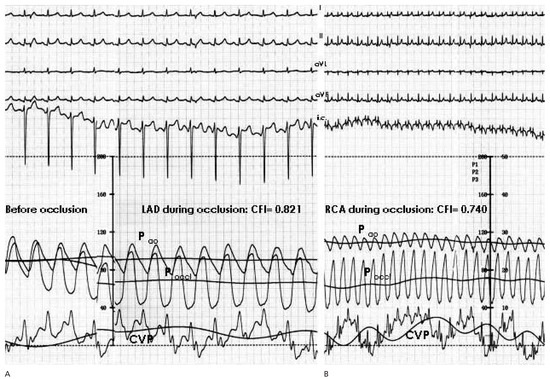

Six Simultaneously Employed Methods to Gauge the Coronary Collateral Flow of the Decade

by Steffen Gloekler, Tobias Rutz and Christian Seiler

Cardiovasc. Med. 2007, 10(9), 298; https://doi.org/10.4414/cvm.2007.01264 - 28 Sep 2007

Viewed by 57

Abstract

Case report. A 59-year-old woman with bronchial asthma and obesity underwent coronary angiography because of exertional dyspnea and atypical chest pain both at rest and sometimes during exertion[...] Full article

Show Figures

Figure 1